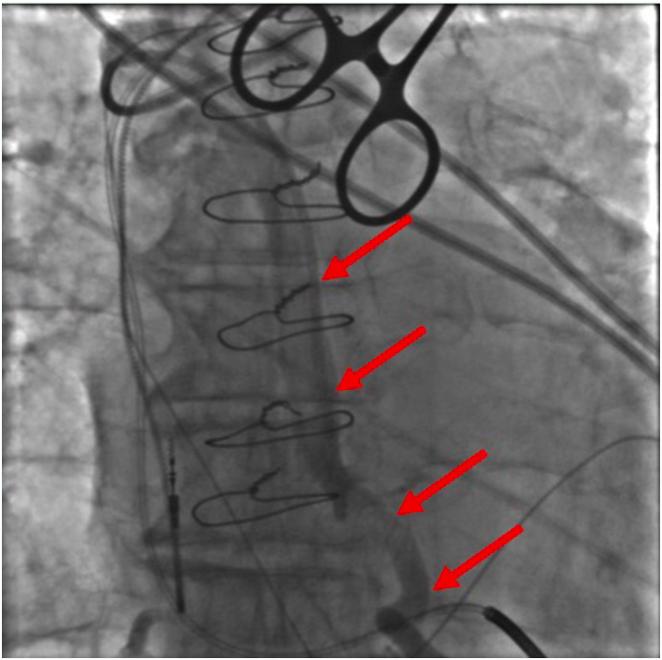

A role for defibrillation threshold testing? A case of ventricular fibrillation refractory to implantable cardioverter-defibrillator shocks in setting of cardiac amyloidosis.

HeartRhythm Case Rep. 2025 Mar 3;11(5):492-495. doi: 10.1016/j.hrcr.2025.02.020. eCollection 2025 May.

Coronary vein defibrillator coil placement in patients with high defibrillation thresholds.高除颤阈值患者冠状动脉静脉除颤器线圈的放置

J Arrhythm. 2018 Dec 3;35(1):79-85. doi: 10.1002/joa3.12136. eCollection 2019 Feb.